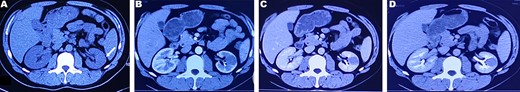

A 37-year-old male underwent a computed tomography scan (CT), which revealed a 2.5 × 1.9 cm slightly lower density ingrown mass in the lower pole of left kidney for 1 month. The patient was asymptomatic and had a history of kidney stones. The shape of the mass was regular, with unclear boundaries. Enhanced CT showed that the enhancement of the mass was lower than that of the surrounding renal parenchyma (Fig. 1). On magnetic resonance imaging (MRI), a circular abnormal signal was detected in the cortical medullary area of left kidney, with an equal signal on T1WI and a slightly low signal on T2WI (Fig. 2A and B). The enhanced MRI scan showed no obvious enhancement in the cortical and medullary phases and a slightly dotted high signal in the excretion phase (Fig. 2C–F). The mass was a space-occupying ingrown lesion with insufficient blood supply. Patients underwent laparoscopic partial nephrectomy and received no postoperative therapy. After the tumor was incised, a 2.3 × 2 cm soft mass that was grayish-white and slightly grayish-yellow was found with clear boundary. Histology (hematoxylin and eosin staining) results showed that the tumor was composed of elongated tubules arranged in parallel. The tubules lined with cuboid and spindle cells set in a small amount of myxoid matrix (Fig. 3A). Most of the tumor cells were round, a few were spindle and elliptical, with eosinophilic nucleoli. Mitotic figures were rare and the atypia is not obvious. Obvious foamy macrophage aggregates could be seen in some areas (Fig. 3B). Immunohistochemical results were as follows: CK7(+), P504S (+), PAX-8(+), CD10(−) (Fig. 3C–F). The Ki67 stain showed proliferation rates up to 5%. The pathological result demonstrated left renal mucin-poor MTSCC. We performed next-generation sequencing (NGS) for case, and the result showed that the tumor mutational burden was 2.74 mutation/Mb. RET gene mutation was considered as a mutation of uncertain significance. The detection of multiple genetic polymorphism sites of tumors shows that it may be slightly sensitive to some chemotherapeutics like gemcitabine. PD-1/PD-L1 immunotherapy may not benefit the patient. The patient was followed up for 8 months after surgery. No evidence of metastasis or recurrence was found.

CT plain scan and enhanced scan of mucus-poor MTSCC. (A) CT scan showed a low-density mass in the lower pole of the left kidney (arrow), unclear boundary, swelling growth in kidney; (B) enhanced CT scan of corticomedullary phase shows tumor mild homogeneous enhancement, (C) nephrography phase, (D) renal excretion phase.